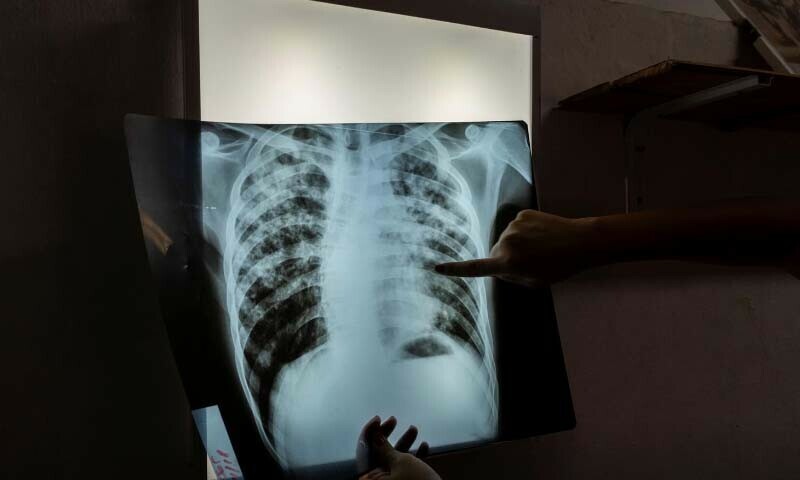

کراچی (ہیلتھ ڈیسک): پاکستان میں گزشتہ 2 برس کے دوران 6 لاکھ 11 ہزار افراد تپِ دق کا شکار ہوئے جبکہ 48 ہزار ایچ آئی وی منفی اور 21 سو ایچ آئی وی مثبت افراد تپِ دق کے سبب انتقال کر گئے لیکن صرف 55 فیصد کیسز ہی رپورٹ ہوسکے۔ رپورٹ کے مطابق یہ بات ’اسٹاپ ٹی بی پاکستان‘ کے وائس چیئرمین ڈاکٹر شرف علی شاہ نے ایک سیمینار کے شرکا سے گفتگو کرتے ہوئے کہی۔

تپِ دق کے کم کیسز رپورٹ ہونے کی وجوہات پر روشنی ڈالتے ہوئے ڈاکٹر شرف علی شاہ نے کہا کہ تپ دق اور اس کی علامات کے بارے میں کج فہمی (آگاہی کی کمی)، علاج کہاں سے کرایا جائے اس بارے میں ناقص معلومات اور سرکاری صحت کی سہولیات پر انسداد تپِ دق ادویات کی دستیابی سے متعلق غلط فہمی، نقل و حمل کی لاگت اور یومیہ اجرت کا نقصان کچھ اہم عوامل ہیں۔

ایچ آئی وی ٹی بی کے مشترکہ انفیکشن پر روشنی ڈالتے ہوئے، ڈاکٹر افشاں عیسانی، صوبائی ٹی بی ایڈوائزر سی ڈی سی سندھ نے کہا کہ تپ دق اور ایچ آئی وی، دونوں انفیکشن ایک دوسرے کو سہولت دیتے ہیں۔

انہوں نے کہا کہ ایچ آئی وی سے متاثرہ افراد میں تپِ دق ہونے کا خطرہ بڑھ جاتا ہے اور دونوں بیماریوں کا اکٹھا علاج زیادہ مشکل ہوتا ہے۔

ڈاکٹر سلیم کاظمی، سینئر ٹیکنیکل ایڈوائزر سی ڈی سی نے کہا کہ عالمی سطح پر تپِ دق کے خاتمے کی حکمت عملی کو نافذ کرنے کے لیے بہت کچھ کیا جا رہا ہے، کچھ حالیہ پیش رفتوں میں حساس تپِ دق کے علاج کی مدت کو بعض صورتوں میں 4 ماہ تک اور منشیات کے خلاف مزاحم ٹی بی کے لیے 6 ماہ تک کم کرنا شامل ہے۔

یہ بات قابل ذکر ہے کہ کثیر الادویاتی مزاحم تپِ دق اس وقت بڑھتی ہے جب مریض کورس مکمل کیے بغیر ادویات لینا چھوڑ دیتے ہیں، یوں وائرس اتنا مضبوط ہو جاتا ہے کہ علاج کی لاگت 10 گنا بڑھ جاتی ہے۔